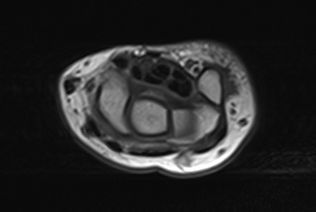

解剖学模块